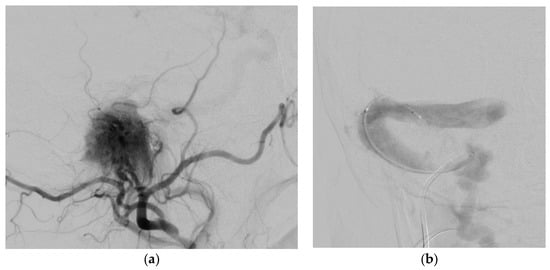

3.3.1. Case 1

3.3.2. Case 2